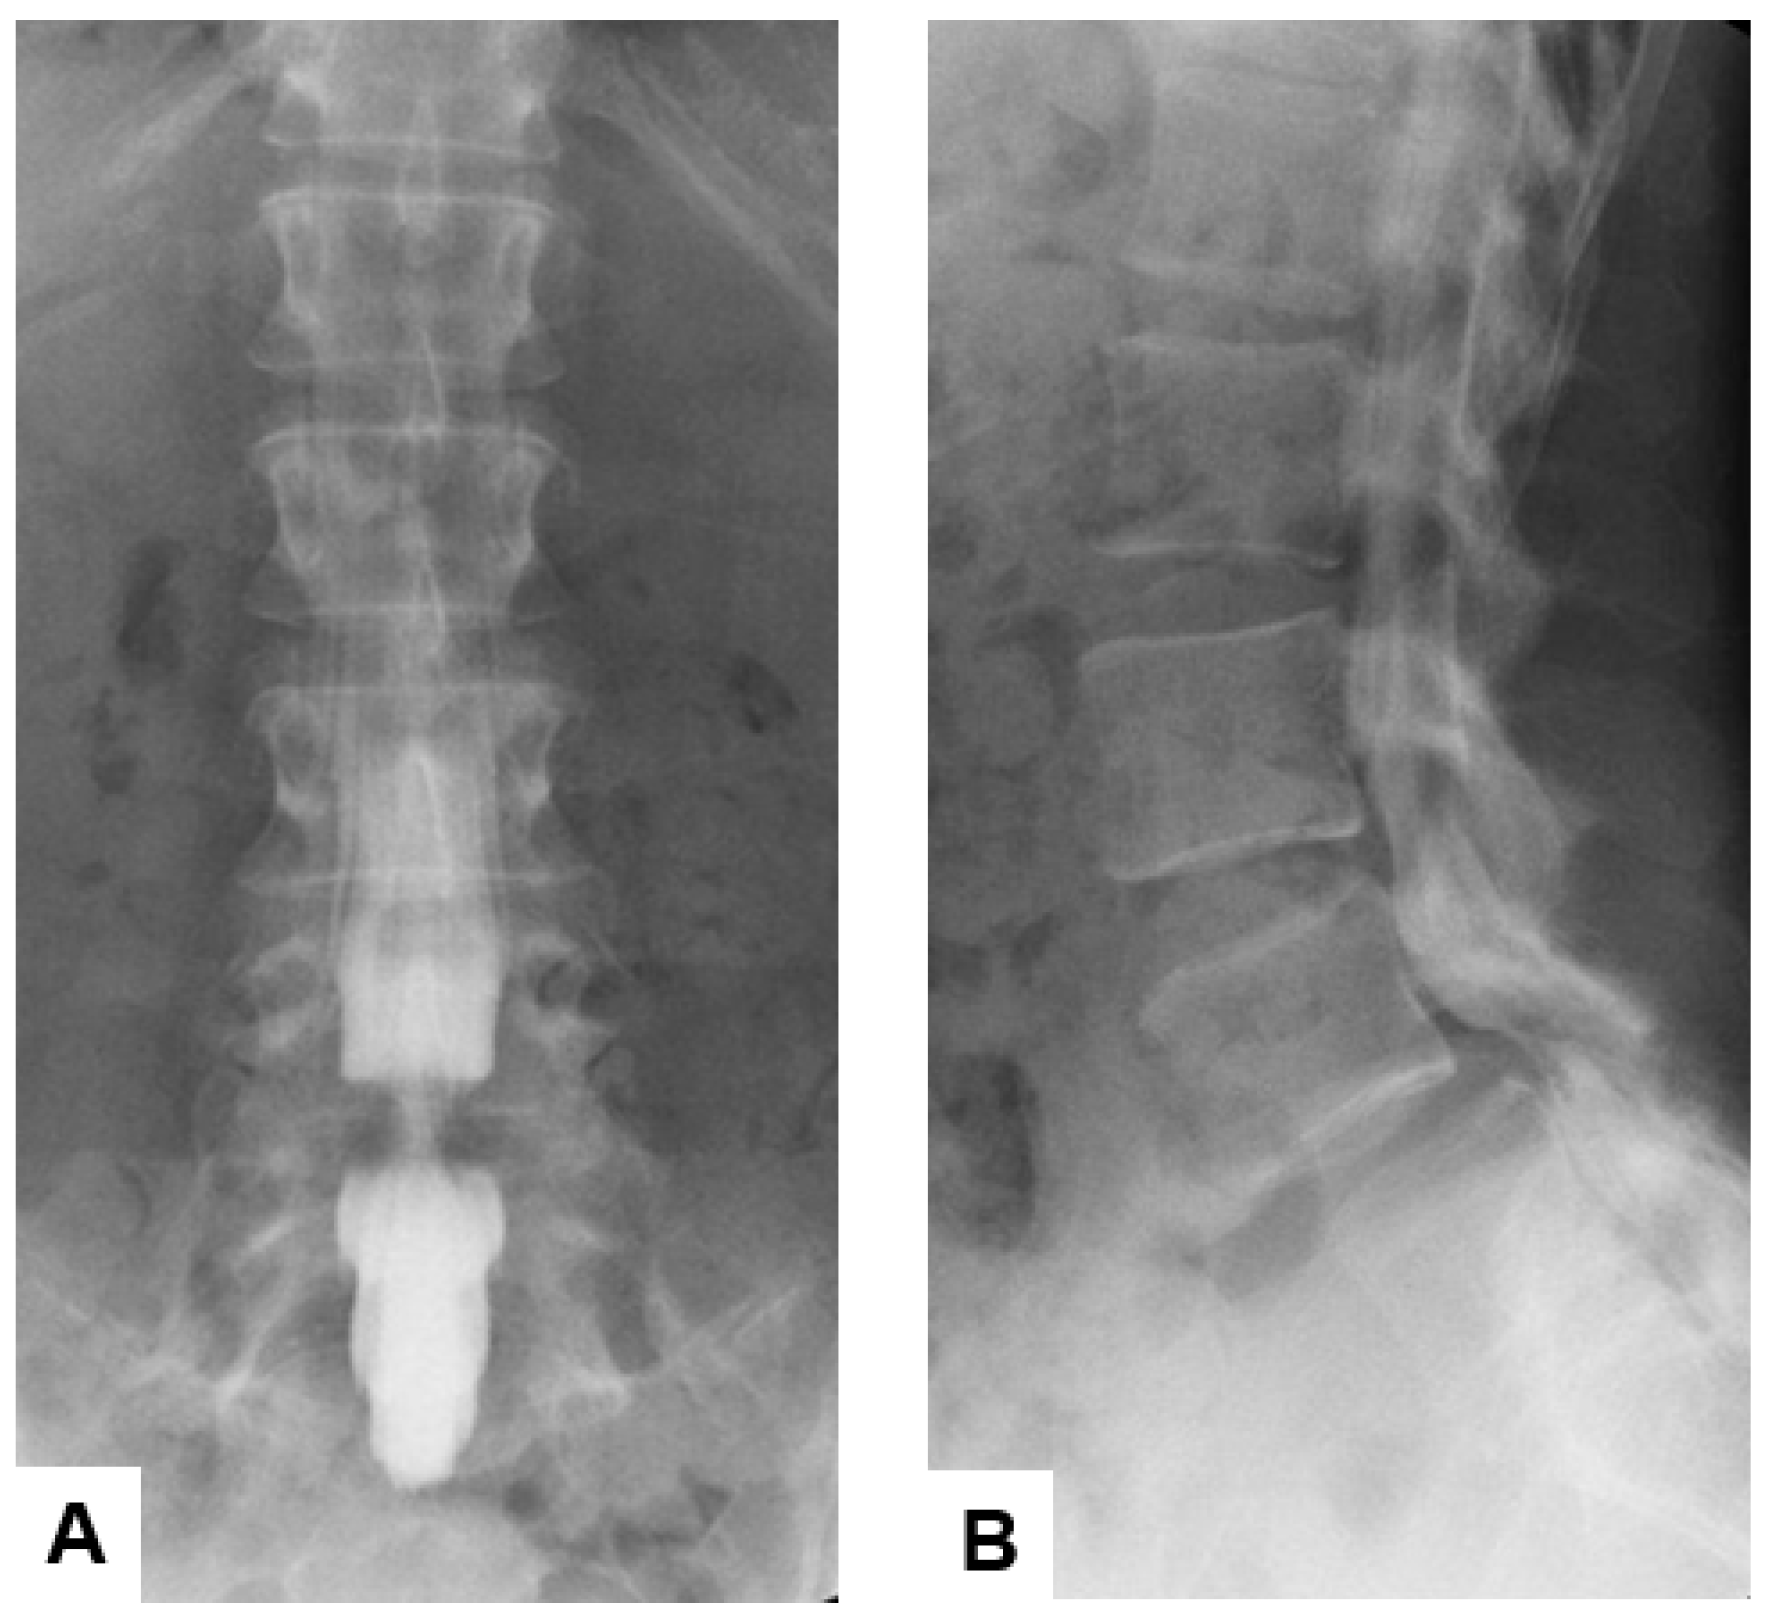

2.1.3. Myelography

This radiological examination evolved in the early 20th century to enhance visualization of the spinal cord, nerve roots, and surrounding structures by injecting a radiopaque contrast agent into the subarachnoid space, followed by X-ray imaging [13]. The shape and contour of the spinal canal can be assessed by this technique, which reveals the compression or displacement of neural elements [14]. Myelography was particularly useful for diagnosing herniated disks, spinal stenosis, and tumors affecting the spinal cord or nerve roots before advanced imaging technologies [15] (Figure 2). The invasive nature and inherent risks of infection, headache, and intracranial hemorrhage due to lumbar puncture make this technique less preferable [16,17,18].

Figure 2. Sixty-five-year-old M, L4 lumbar degenerative spondylolisthesis, (A) anteroposterior lumbar myelography, (B) lateral lumbar myelography. The filling defect is shown at L4/5.